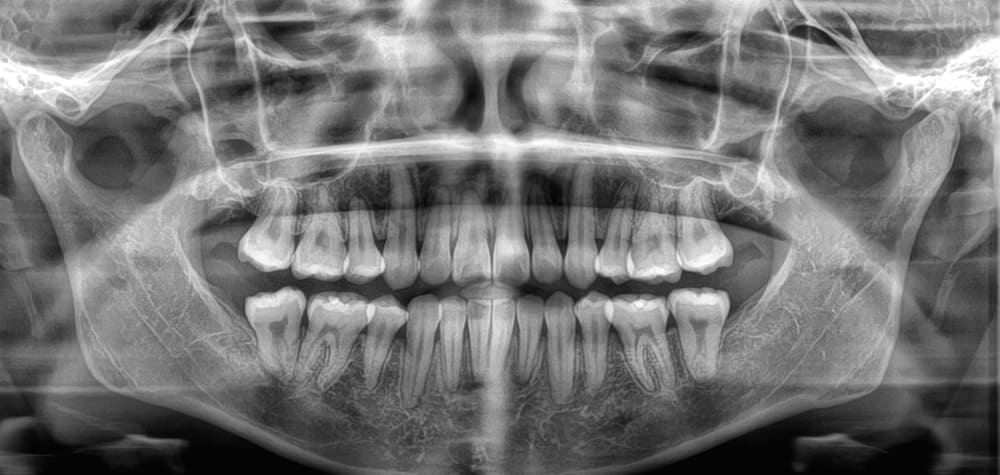

パノラマレントゲン写真です。

上下左右の親知らずの埋伏が認められます。

矯正治療中にタイミングを見てすべて抜去する予定です。

※親知らずの抜歯は保険適用になるので大学病院を紹介させていただき、抜歯を行うことが多いです。

パノラマレントゲン写真です。親知らずは、4本とも抜歯されています。